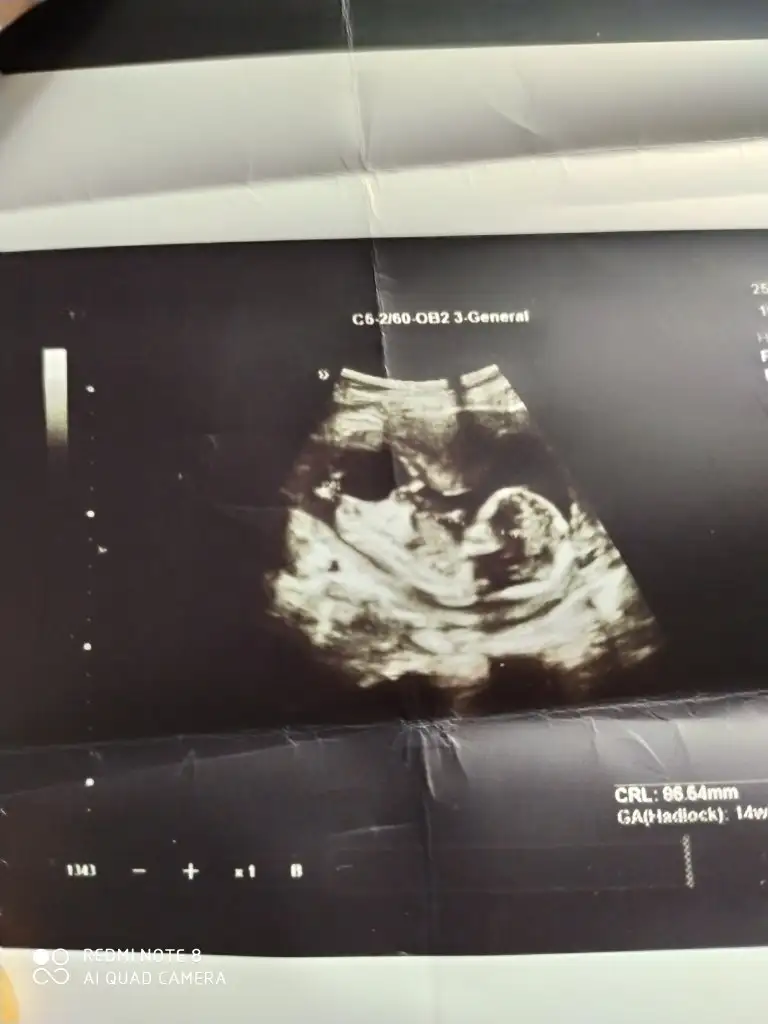

benim bebeğimde tahminde bulunur musunuz 12 haftalıklenki usgsiNet değil usg erkek olabilir

Net değil o yüzden malesef yorum yapamadımbenim bebeğimde tahminde bulunur musunuz 12 haftalıklenki usgsi

bunada bakabilmisiniz 12+4 de çekilenKese %75 nub %85 en iyi nub tahmini onun için 11 12 13 haftalar olmalı